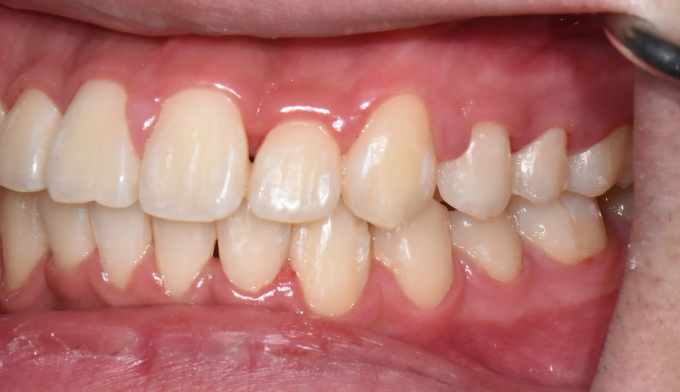

불규칙앞니

불규칙한 앞니를 교정하기 위해선 공간을 만들어야 합니다.

악궁이 좁은 경우에는 확장치료를, 그렇지 않으면 전체 치아를 후방이동시키거나 치아를 삭제하기도 합니다.

이번에는 악궁이 좁은 경우에 해당됩니다. 그 정도가 심해, 윗니 일부가 아랫니보다 안쪽으로 들어가있습니다.

상악확장장치를 통해 악궁을 넓혀주고 치아를 배열해줍니다.

치료기간은 15개월 소요되었습니다.